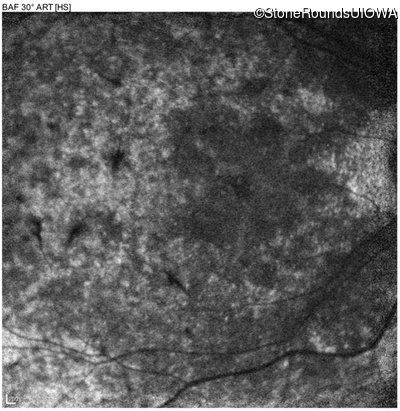

Blue Autofluorescence - Right - 10/700 sc

Exemplar